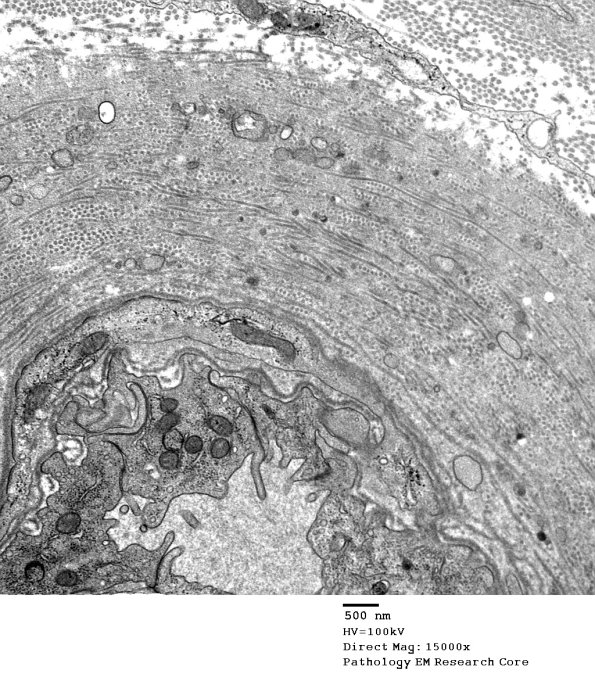

1B2-5 Progressively higher magnifications of the wall of this vessel shows it is composed of collagen oriented in longitudinal and circumferential patterns. (electron micrographs)